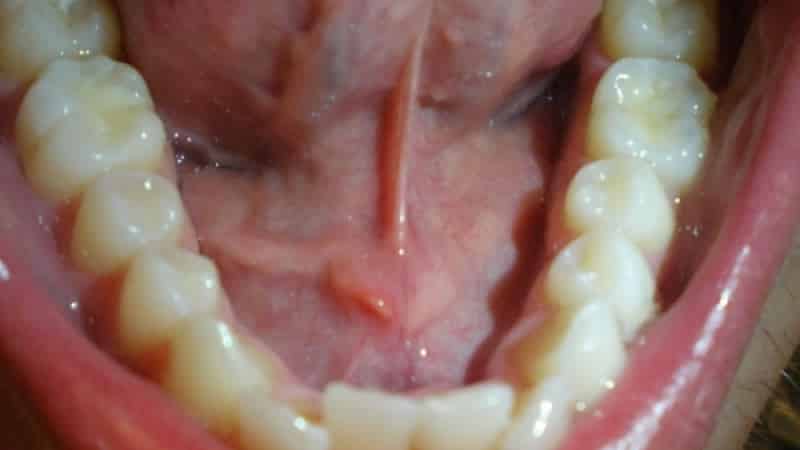

Часто болевые ощущения связаны с повреждением мягких тканей или воспалением уздечки. Особое внимание стоит уделить уздечке, которая может быть патологически короткой и испытывать повышенные нагрузки по сравнению с нормальной длиной.

Воспаление уздечки под языком, или френит, может проявляться различными симптомами, которые могут варьироваться по степени выраженности. Основные признаки воспалительного процесса включают:

- Отек: Воспаление может приводить к отеку уздечки, что делает ее более заметной и может затруднять речь и глотание.

- Покраснение: Участок вокруг уздечки может быть покрасненным, что свидетельствует о воспалительном процессе.

- Кровоточивость: В некоторых случаях возможно появление небольших кровотечений, особенно если уздечка повреждена или травмирована.

- Визуальный осмотр: Специалист осматривает уздечку и окружающие ткани на наличие покраснения, отека, язв или других изменений.